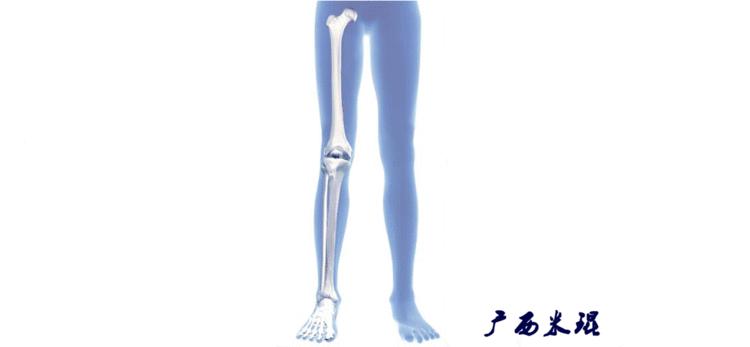

(2)机械轴

机械轴是连接近端和远端关节中心点的直线。

机械轴要分前后位及侧位,站立前后位(也就是冠状面)股骨头中心与踝关节中心的连线通过膝关节中心,这是下肢的机械轴线,也就是下肢力线,常说Mikulicz线。冠状面的力线评估在临床工作中最常用、最基础、最重要。

站立侧位(矢状面)股骨头中心与踝关节中心的连线也通过膝关节中心,这也是下肢的机械轴线,这也是下肢力线。

矢状面的下肢力线常常被医生忽视,其实它的改变也是膝关节疼痛的常见原因。

我们说了这么多照片的下肢力线测量,体表也是可以粗略测量的,自股骨头中心至踝关节中心拉一直线,髌骨中心点位于此直线上;自髂前上棘至踝关节中心拉一直线,髌骨中心点位于此直线内侧;自髂前上棘至第1、2趾间拉一直线,髌骨中心点位于或接近此直线。

(3)垂直轴

也就是下肢的负重轴,它是身体的纵轴线,与地面垂直,由于双髋比双踝的距离宽,所以垂直轴与下肢力线(机械轴)存在3°的外翻。